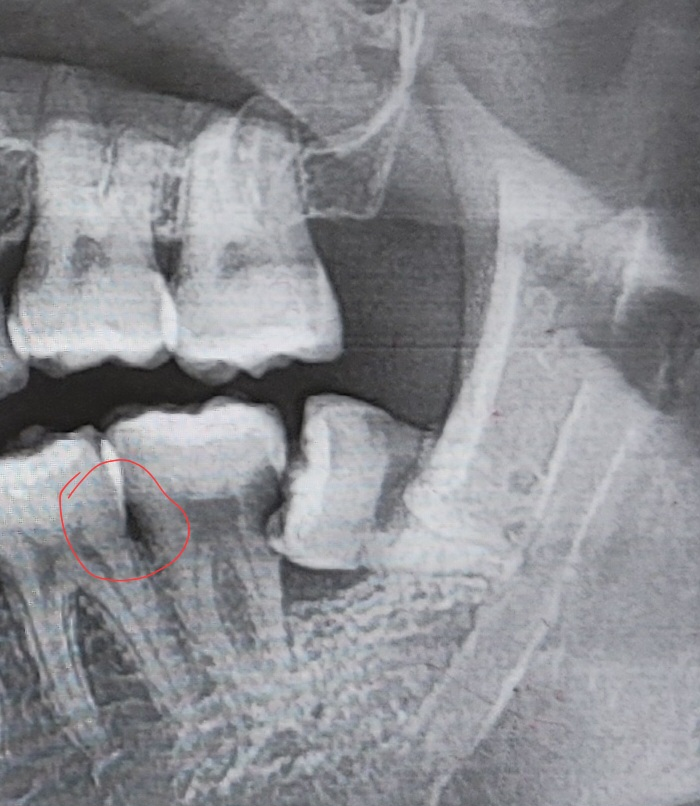

제가 3주전에 어금니를 발치하고 픽스쳐 식립했는데요 사진은 바로 옆 어금니뒷 면 입니다. 두 번째 사진은 발치 전 엑스레이 사진입니다. 마지막은 식립 이후 사진입니다.

아니면 엑스레이 빨간 동그라미처럼 원래 있던 구멍인거고, 발치 후 회복기간동안 옆 이빨이시릴 수 있는걸까요? 발치 전까진 한번도 시린적이 없었어요

• 2번 째 사진

치아 발치시에 옆에 있던 치아의 충치 부위가 노출 되면서 시리거나 통증이 발생할 수 있습니다

x-ray 상에서는 심한 충치로 보이지는 않으나 시린 증상이 계속해서 나타난다면 치료 받으시는 것이 좋습니다